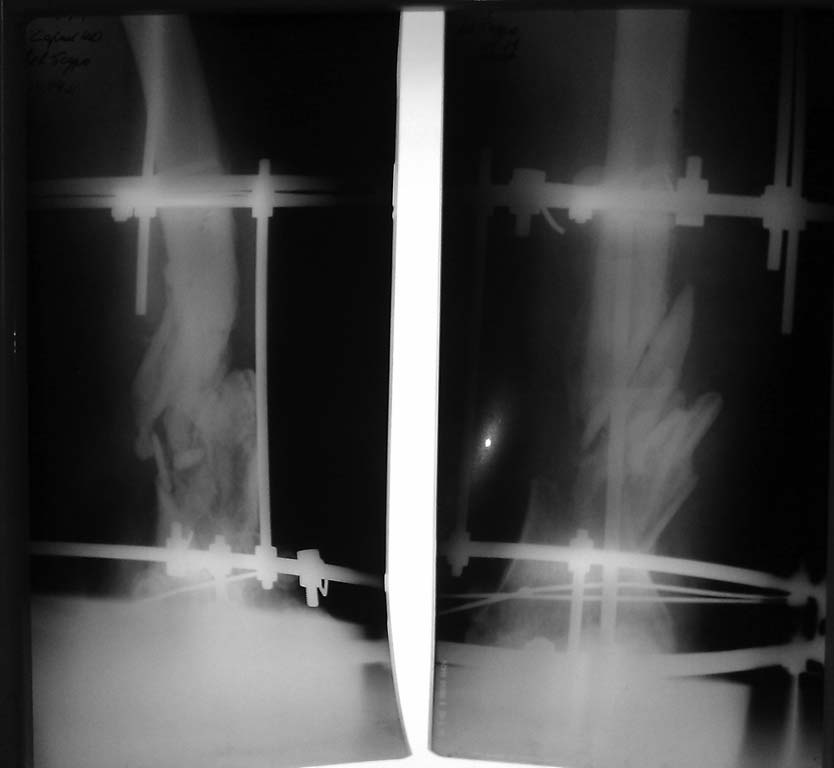

Ложный сустав н/3 бедра

Год назад производственная травма с обширной раной н/3 бедра. Оперирован на Севере спице-стержневым аппаратом.

В анамнезе -В настоящий момент рана бедра зажила, аппарат Илизарова снят. Из спицевых ран гнойное отделяемое. Из области раны отделяемого не было.

Как мне мыслится, при отсутствии гнойного процесса открыть место перелома, периостально выделить осколки, произвести интрамедуллярный остеосинтез ретро-, или антеградным стержнем и жизнеспособные осколки по возможности уложить в дефект,вокруг штифта.

Пациент лечится, полагаю, достаточно времени, чтобы сделать снимки на всем протяжении с захватом обоих суставов. И показать для обсуждения именно такие снимки, а не огрызки.

Пока по увиденному думается про закрытый интрамедулярный остеосинтез гвоздем антибактериальным покрытием (можно и анте, и ретроградно) без открытых вмешательств на зоне несращения.

Объясните пожалуйста, как можно установить штифт не открывая места перелома в данном случае, ведь осколки перекрывают костно-мозговой канал и не дадут правильно попасть в дистальный отломок. Растянуть конечность по оси, что бы осколки приняли правильное местоположение, не закрывающее канал для штифта, кажется затруднительным, т.к. образовался уже малоподвижный конгломерат из этих осколков и окружающих мягких тканей.